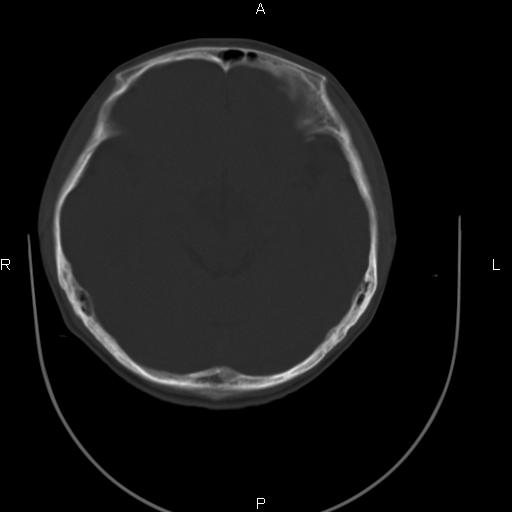

标题: CT27115:大家看一看,这孩子的颅骨表现? [打印本页]

标题: CT27115:大家看一看,这孩子的颅骨表现?

两名中学生打架,脑质内未见异常,未上传。

两例——颅骨结构正常,未见明显骨折征象。

感觉第2个颅缝密度高,额顶部板障有点厚,正常变异?地中海贫血?